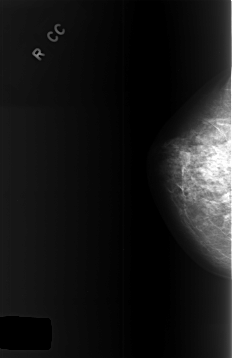

C_0372_1.RIGHT_CC

RIGHT_CC LINES 5728 PIXELS_PER_LINE 3712 BITS_PER_PIXEL 12 RESOLUTION 50 NON_OVERLAY